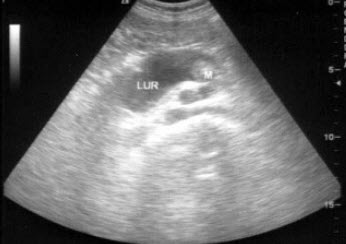

44、单项选择题

男,63岁,因左侧腰部疼痛不适伴无痛血尿1月余就诊,B超显示左肾集合系统分离3.9cm,如图所示,最可能的诊断为()